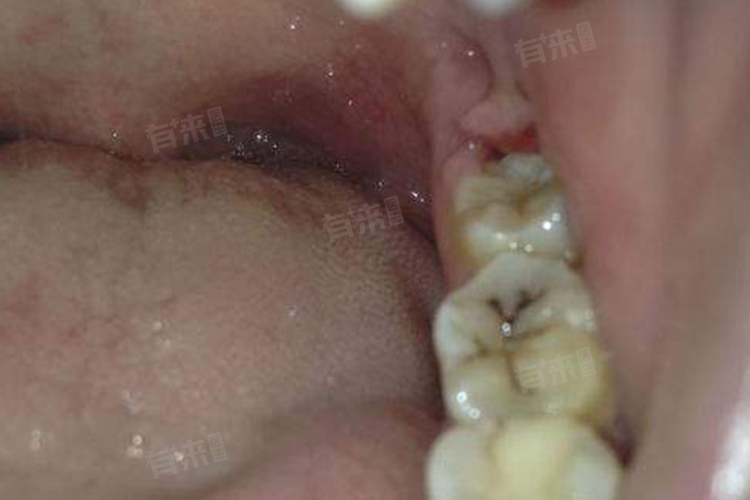

2、导致邻牙移位:后槽牙缺失后,邻牙失去支撑,会逐渐向空缺处倾斜、移位。邻牙位置改变,会使牙齿排列变得稀疏,易造成食物嵌塞,引发龋齿、牙周炎等口腔疾病。而且邻牙移位后,后续补牙难度增加,对口腔整体健康威胁增大。

3、破坏咬合关系:后槽牙在维持上下牙正常咬合中起关键作用,缺失后,对颌牙因无相对咬合的牙齿限制,会逐渐伸长,导致咬合紊乱。咬合紊乱不仅影响咀嚼效率,还会引发颞下颌关节紊乱综合征,出现关节疼痛、弹响、张口受限等症状,严重影响日常生活。